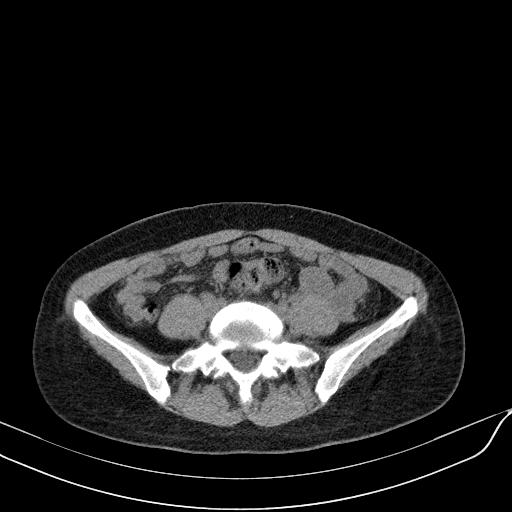

标题: CT23965:无外伤史,下腹痛 [打印本页]

标题: CT23965:无外伤史,下腹痛

肠道未准备,继续往下扫,乙状结肠占位不排除。建议钡灌或结肠镜检查。

乙状结肠占位不排除

未见明显异常改变,做个气钡双重造影除外一下结肠病变,无外伤史为啥不常规喝泛影葡胺水对比剂再扫ct呢?

回肠间质瘤?

肠道肿瘤,建议行钡剂灌肠检查。